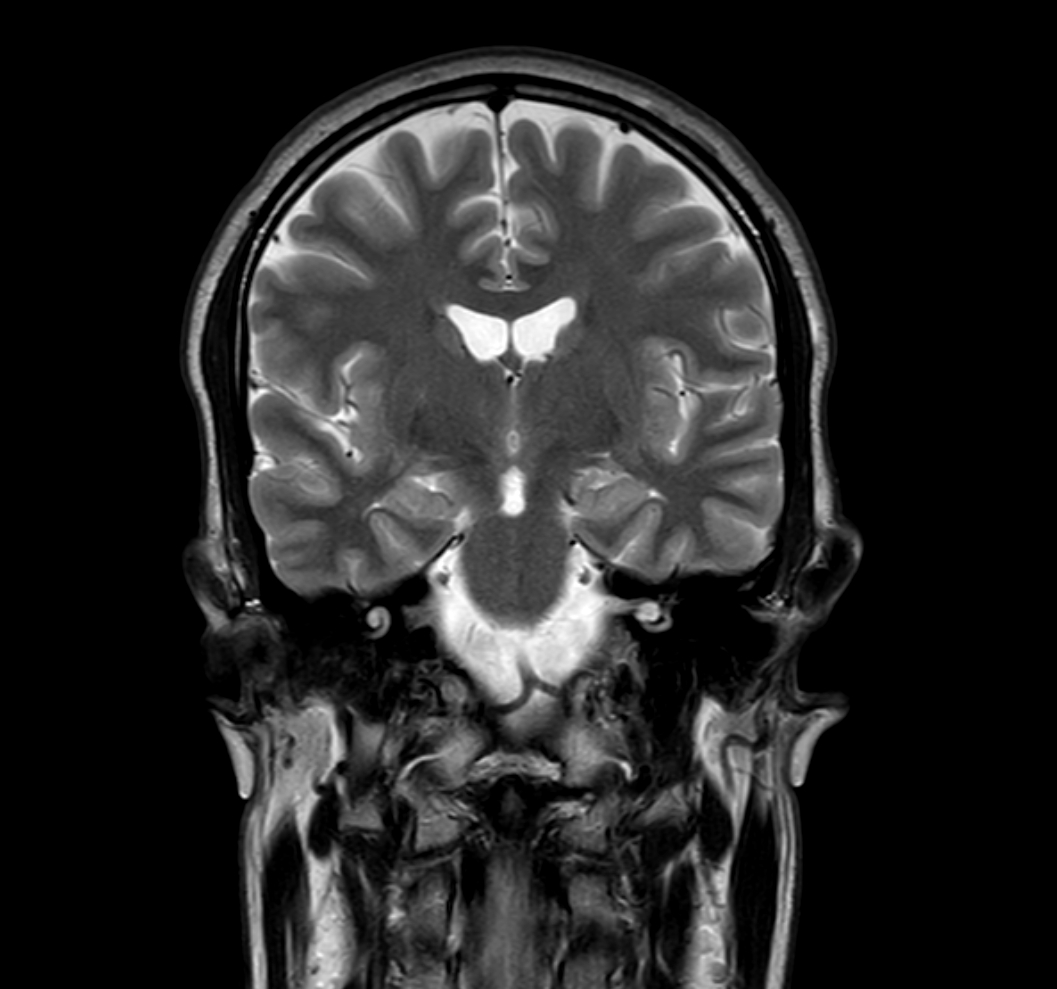

Coronal T2w TSE with ComforTone